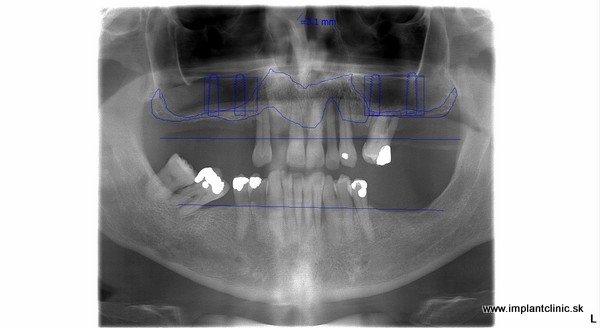

RTG snímka pred ošetrením

Ľudia považujú úbytok kostného tkaniva po strate zubov za bežný jav starnutia. Avšak pokroky v modernej  implantológii nám umožňujú riešiť problematiku úbytku kosti a poskytujú nám spôsoby, ako predchádzať strate kostnej hmoty a ako ju úspešne regenerovať.

Dôvodov prečo sa čeľustná kosť oslabuje je viac. Najčastejšie je to výsledok neliečených ochorení parodontu. Na miestach kde nám chýbajú zuby kosť nie je dostatočne stimulovaná a dochádza k jej artrofii.

Oslabená čeľustná kosť nemusí byť kontraindikáciou pre zubné implantáty. Ponúkame Vám prípad pacienta z Implantclinic, ktorému sme aj napriek oslabenej kosti úspešne zaviedli zubné implantáty a tým dopomohli k plnohodnotnejšiemu životu. Už sa nemusíte obávať, že z dôvodu úbytku kosti, nebudete vhodným kandidátom pre zubné implantáty a jedinou formou náhrady by bola snímateľná protéza.